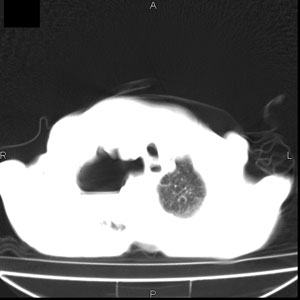

患者男,77岁,于3日前从树上摔下,头部查ct示蛛血,硬膜下出血,上腹部ct未见明显异常,右侧胸腔积液,左侧如常。肺部拍片示右侧肋骨多发骨折住院后今日来查肺部ct,我看到的是1。右侧胸腔血气胸并右肺上叶,中叶压缩性肺不张,2。右肺下叶肺挫伤并多发肋骨骨折,肌内及皮下积气3。左侧少量胸腔积液,我想请教的是3天前左侧胸腔里没有积液今天怎么出现了呢,是什么原因呢?请讨论。